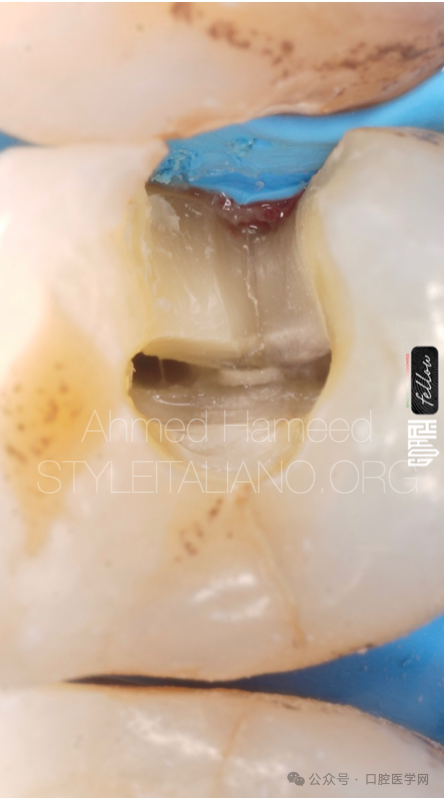

图9

去除龋坏后,我们可以看到裂纹线延伸到牙本质中,这意味着我们需要磨除更多的组织来追踪裂纹。

图10

这张照片显示了裂纹如何向牙髓延伸,导致牙髓坏死,因为从髓腔可以明显看出,裂纹仍在向根方延伸。